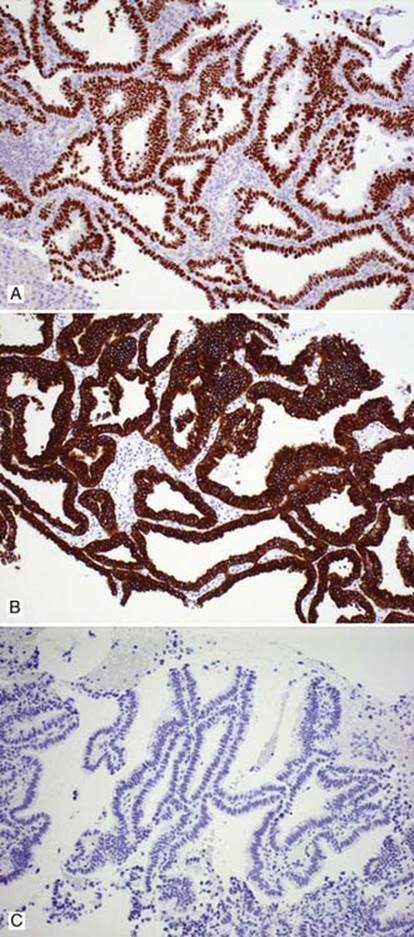

• Nonmucinous AIS has similar immunoprofile as adenocarcinoma of lung with positive TTF-1, CK7, and negative CK20

Fig 3 Adenocarcinoma in situ. Nonmucinous AIS with positive TTF-1 (A), positive CK7 (B), and negative CK20 (C).